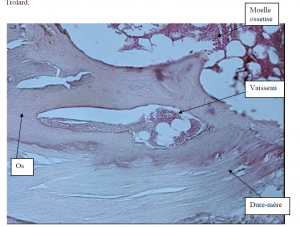

Photo INSERTIONS DE LA DURE-MERE SUR LE RACHIS Une anatomie redécouverte 32

Photo INSERTIONS DE LA DURE-MERE SUR LE RACHIS Une anatomie redécouverte 33